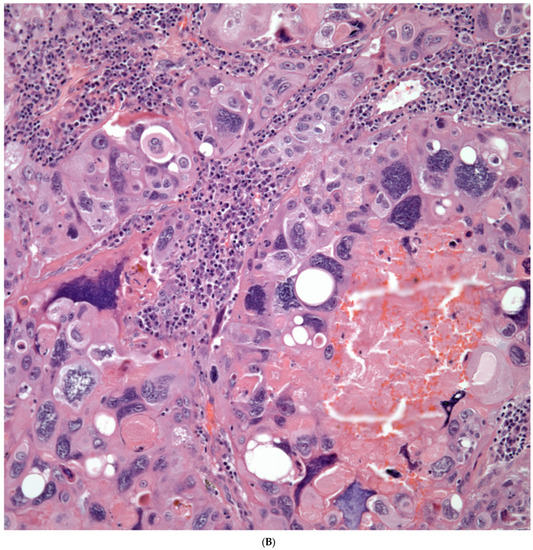

Sarcomatoid carcinomas: These tumors show a tightly packed spindle cell proliferation composed of slender cells with fusiform nuclei and inconspicuous nucleoli, replacing normal lung parenchyma. The tumors are well delimited but not encapsulated (Figure 1). Cellular atypia is variable and may show areas of mild to moderate to marked atypia. Mitotic figures also vary and may be inconspicuous or may be evident with the presence of atypical mitotic figures (Figure 2A,B). In high-grade tumors, the presence of necrosis and hemorrhage is prominent and is mixed with the neoplastic component. Important to recognize is that sarcomatoid carcinomas may be associated with areas of otherwise conventional non-small cell carcinoma such as adenocarcinoma or squamous cell carcinoma (Figure 3A,B). In addition, sarcomatoid carcinoma may also show the presence of bizarre giant cells admixed with the spindle cell component (pleomorphic carcinoma) (Figure 4).

Giant Cell Carcinomas: These tumors may show predominantly a neoplastic cellular proliferation composed exclusively of multinucleated giant cells or a predominantly giant cell carcinoma (Figure 5A,B) or associated with a conventional non-small cell carcinoma like adenocarcinoma or squamous cell carcinoma. The giant cell carcinoma may show giant cells of the syncytiotrophoblastic, osteoclastic, or null cell type. The giant cell carcinomas of the null cell type characteristically show a prominent inflammatory background and giant cells engulfing inflammatory cells (emperipolesis) (Figure 6A,B). The tumors composed of osteoclast-like giant cells show giant cells like those described in bone tumors (Figure 7A,B).

Figure 5.

(A) Predominantly giant cell carcinoma; (B) Marked atypia and numerous multinucleated malignant giant cells.